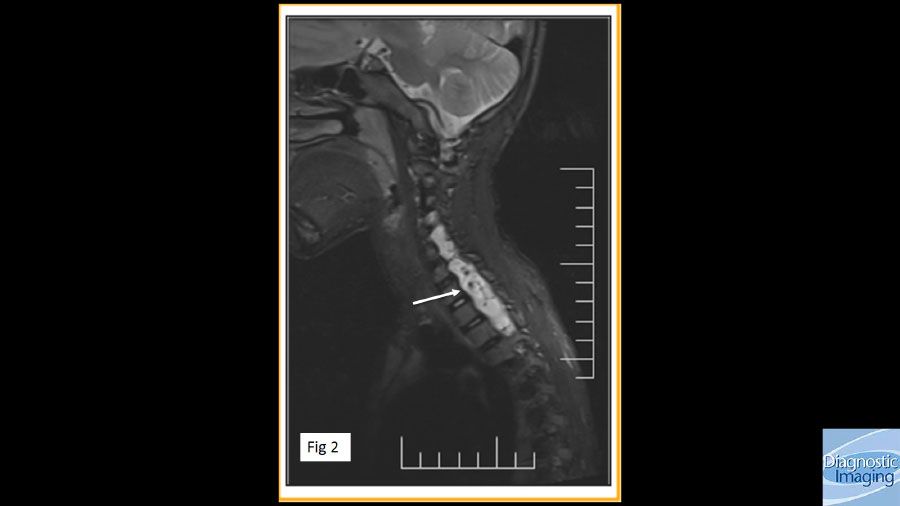

Case History: 7-year-old male with left upper limb weakness that started two years following a motor vehicle accident.